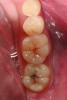

A 48-year-old patient presented with an old, failing Class I alloy restoration and showed recurrent decay on the lower molars (Figure 9). After the existing alloy was removed, the remaining tooth structure was evaluated. It was determined that despite the significant extent of caries present, it would be possible to perform a minimally invasive procedure using an injectable composite resin and an RMGI (Figure 10).

After removing the infected dentinal layer, a caries-detection stain was used to determine if further tooth removal would be necessary. On removal of all infected dentin, a chlorhexidine gluconate swab (CAVITY CLEANSER™ 2% Chlorhexidine Digluconate, BISCO, Inc.) was used to remove any surface bacteria on the prepared site. Next, a polyacrylic acid scrub was performed for 20 seconds to condition the dentin surface. An RMGI (GC Fuji II LC) was sculpted and light-cured to cover the affected and unaffected dentin.4,13,18,19 After the RMGI liner was fully cured, a micropreparation diamond bur (830RM.FG.009, Komet USA) was used to refine the internal form of the preparation. Marginal beveling to a 45° taper was completed along the cavosurface of the final tooth preparations.15

A dentinal adhesive resin was used to further seal the cavity preparation. Using a seventh-generation adhesive (ALL-BOND UNIVERSAL), a polymer chain union was created between the composite resin and RMGI.16 Following proper placement of the adhesive resin, an injectable composite resin (G-ænial Universal Flo) was placed over the RMGI, causing intimate union between the materials. An incremental build-up technique using the injectable composite resin was then easily employed to anatomically reconstruct the tooth.21-23 Because the selected resin has an excellent depth of color, a natural-looking result was achieved with a single shade of resin.24,25

Accurate contouring and margination was achieved using Q-Finisher composite resin finishing burs for final finishing. A composite finishing (H247UF.314.009, Komet USA) (H274Q.314.018, Komet USA) was used to develop initial occlusal anatomy, after which a 30-fluted finishing bur refined the occlusal surface smoothness. Finally, using one-step microdiamond-infused finishing points (C9479, Komet USA) and a microdiamond polishing paste, a natural-looking finish and polish was achieved (Figure 11).27

CASE 2 RESTORATIVE TREATMENT (9.) Failing Class I alloy restoration and fissure decay on lower molars. (10.) Modern minimally invasive dentistry preparations on both molars. Notice the moderate decay lesion under the failing alloy. (11.) After placement of resin-modified glass ionomer liner, an injectable composite resin is the ideal material for these conservative restorations.